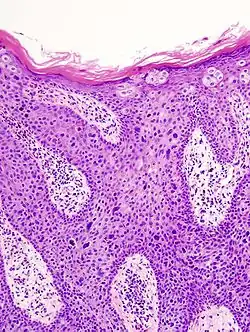

In situ disease

Bowen's disease is essentially equivalent to and used interchangeably with cSCC in situ, when not having invaded through the basement membrane.[12] Depending on source, it is classified as precancerous[13] or cSCC in situ (technically cancerous but non-invasive).[48][49] In cSCC in situ (Bowen's disease), atypical squamous cells proliferate through the whole thickness of the epidermis.[12] The entire tumor is confined to the epidermis and does not invade into the dermis.[12] The cells are often highly atypical under the microscope, and may look more unusual than the cells of some invasive squamous-cell carcinomas.[12]

cSCC in situ, high magnification, demonstrating an intact basement membrane.[12] -

cSCC in situ -

cSCC in situ